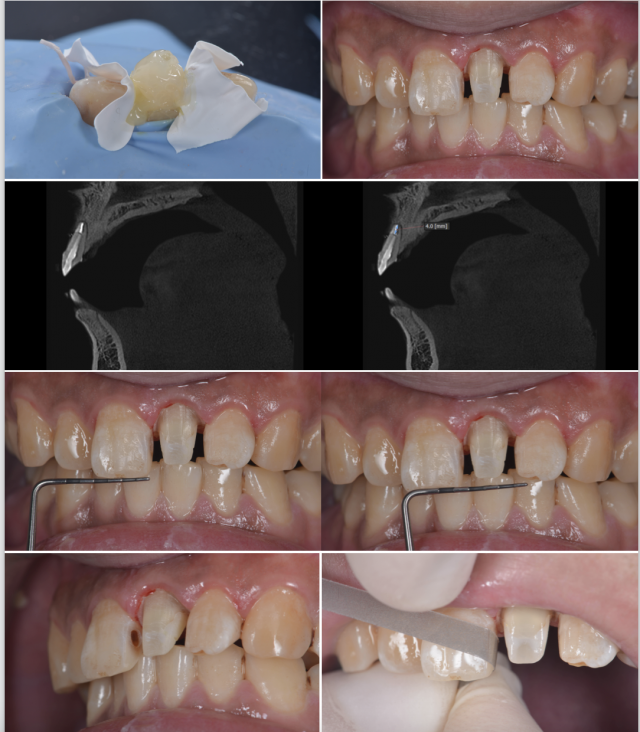

A.树脂核堆塑;B.牙体预备;C.根尖保留4mm根充物植入纤维桩的术后影像;D.两中切牙近远中比例检测;E.11去龋;F.11树脂充填,11、22邻面去釉抛光

牙体预备排龈 A.唇面观;B.?面观

检查:21临时牙存。

处理:口内试戴全瓷冠,检查就位情况、冠边缘密合无悬突、邻接关系紧密、外形及颜色患者满意、无咬合高点及咬合干扰,粘固修复体。

对患者术后卫生指导及术后维护治疗,包括定期洁牙,正确使用软毛牙刷、牙线等。

术后随访 一个月后患者复诊再进行评估,此后每6个月复查一次。

全冠边缘位置设计(龈上、齐龈、龈下):对于非美学区域,通常制备齐龈或龈上边缘,以减少预备过程中牙龈组织损伤,增加修复体的自洁性;而在美学区域,通常选择龈下边缘。本病例中因患者口腔卫生维护不是太理想,牙面由于菌斑生物膜的堆积导致牙龈炎,再者该患者属于低位笑线,结合患者实际情况,从远期效果考虑,与患者沟通,最终将该修复体边缘确定为齐龈边缘。